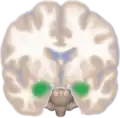

Dorsal view of the amygdala in an average human brain

Frontal view of the amygdala in an average human brain